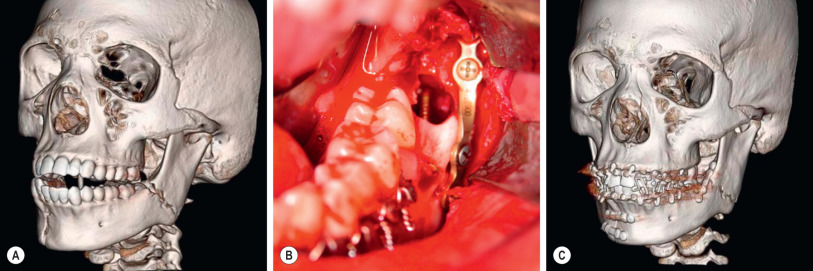

Angle fractures can be addressed with an external oblique ridge (Champy) plate if simple and minimally displaced, or via a vestibular approach with trocar or external approach if complex or widely displaced. Damaged third molars or those interfering with reduction should be removed to allow for reduction and fixation of the fracture. For the intraoral (Champy) approach, after exposure and reduction of the fracture, a 2.0-mm miniplate is bent to follow the contour of the external oblique ridge and is fixated with 6- to 8-mm screws. For the trocar + vestibular incision or external (Risdon) approach, after exposure and reduction of the fracture, a curved 2.4-mm plate is bent to follow the contour of the inferior border of the angle of the mandible, and is fixated using bicortical screws measured with a depth gauge, placed via the trocar or directly using the Risdon approach. As with the symphyseal, parasymphyseal, and body fractures, IMF is removed and pre-trauma occlusion ascertained ( Fig. 3.10.2 ).

Incisions are closed using either 4-0 polyglactin (Vicryl, Polysorb) or 4-0 chromic sutures, and the patient is placed into IMF with 26-gauge wires ( Fig. 3.10.3 ).